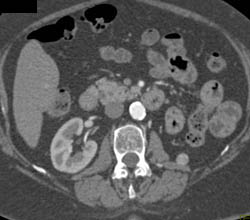

Acute Pyelonephritis Right Kidney